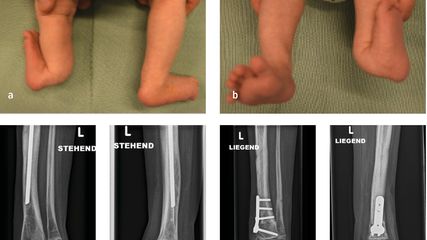

Angeborene Fehlstellungen des Unterschenkels

Kongenitale Deformitäten des Unterschenkels gehören zu den seltenen, aber medizinisch bedeutenden und operativ herausfordernden Diagnosen der Kinderorthopädie. Eine differenzierte ...